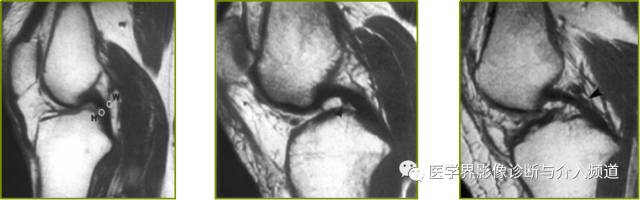

左图矢状面质子密度加权像示:板股前韧带(Humphry韧带)和板股后韧带(Wrisberg韧带)的常见位置;中图示H韧带;右图示W韧带。